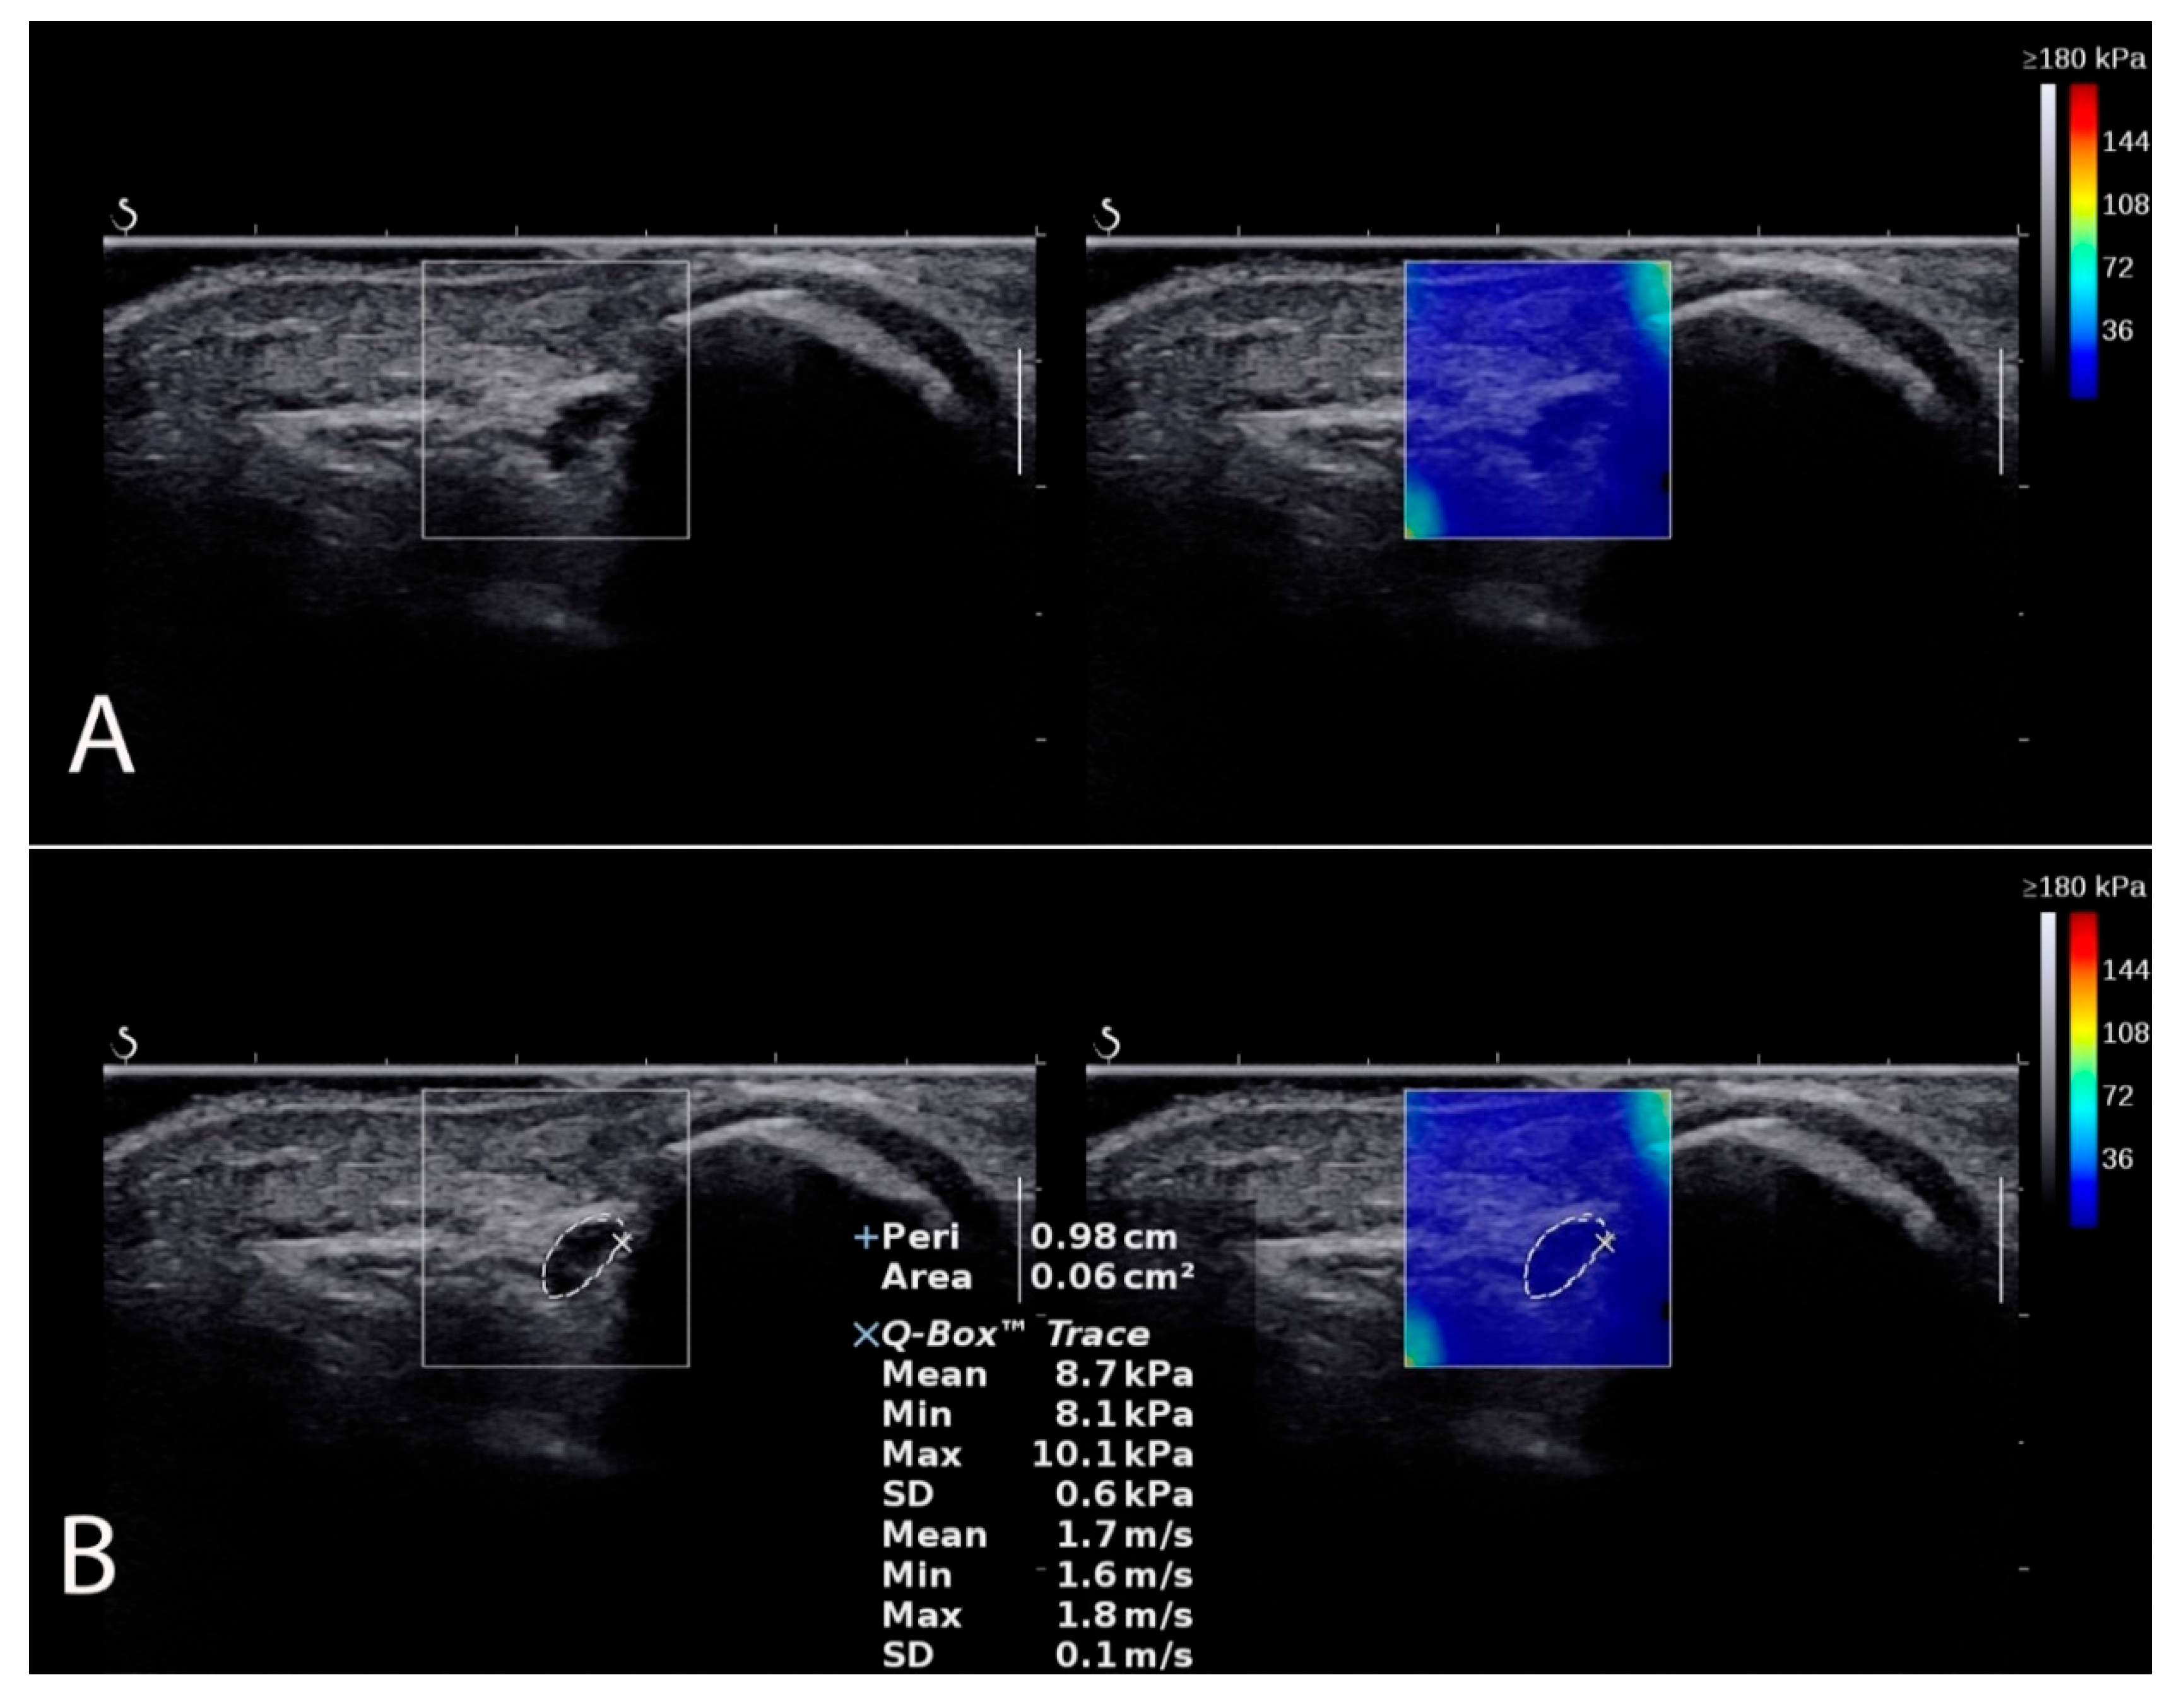

Figure 2.

Ulnar nerve localization in SWE mode (A). Measurement example (B) of CSA, shear modulus, and TRACE.

CSA, shear modulus, and TRACE examinations were performed in the SWE mode in four positions of the elbow joint (full extension, 45° flexion, 90° flexion, and maximum flexion) with a transverse probe position (Figure 2). The CSA is the cross-section of the ulnar nerve in the ulnar tunnel measured in square millimeters (mm2). The share modulus evaluated ulnar nerve stiffness in kilopascals (kPa). The TRACE, in turn, is the circumference of the ulnar nerve over the inner hypoechoic border of the ulnar nerve measured in millimeters (mm). To control and minimize the pressure of the head on the skin, a correspondingly large amount of hydrogel was applied to the area examined. After imaging the ulnar nerve in the cubital tunnel, its transverse scans were recorded in each angular position (controlled with a goniometer), always starting with full extension, then 45° angle, 90° angle, and maximum flexion of the elbow, with the measurement procedure repeated in the same order three times. The means of three measurements were used for the final analysis.